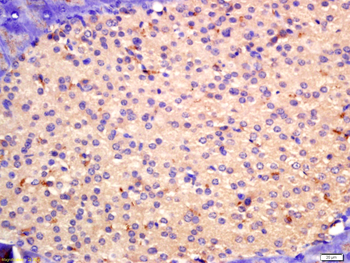

10 μg, 100 μgChemerin Rabbit Polyclonal Antibody [orb156351]

IF, IHC-Fr, IHC-P

Bovine, Porcine

Human, Mouse, Rabbit, Rat

Rabbit

Polyclonal

Unconjugated

100 μl, 200 μl, 50 μlGoat anti-CYP26B1 Antibody [orb19329]